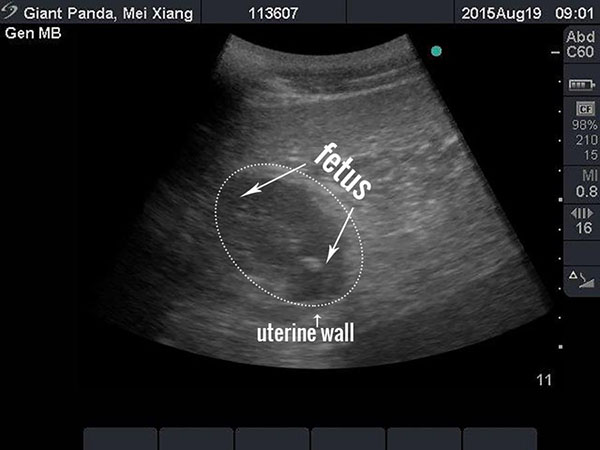

An ultrasound image of the National Zoo's giant panda Mei Xiang is pictured in this handout photograph taken and released on August 19, 2015. [Photo/Agencies]

On Wednesday morning, veterinarians detected a developing fetus during an ultrasound procedure for Mei Xiang, one of the two adult giant pandas which arrived here from China on Dec 6, 2000, the zoo said in a statement.

"Based on the size of the fetus, which is about four centimeters, veterinarians estimate that Mei Xiang could give birth early next week, or possibly in early September," said the statement.